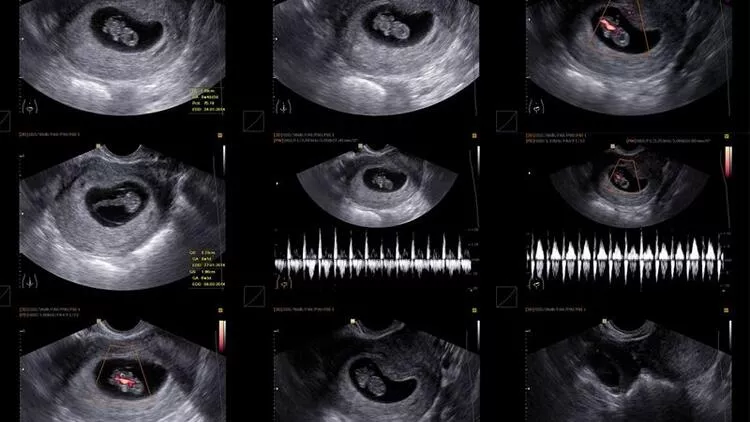

Gebelik kesesi, bebeğin hamilik süresince gelişmiş olduğu yerdir. Rahim içerisinde siyah ve yuvarlak bir oluşum şeklinde görülmektedir. İçerisinde amniyon sıvısı dolu olarak görülmektedir. Keseler şekil olarak yuvarlaktır. Etrafında ise rahmin iç tabakası çevrili şekildedir. Kesenin düzgün sınırlara sahip olması ise normal gebelik olduğunu düşündürmektedir.

7 Haftalık Gebelik Kese Var Bebek Yok!

Genel olarak ilk defa hamilelik yaşayanlar biraz panik ve korku halinde olmaktadırlar. Bu sebepten dolayı da birçok farklı sorun algılarlar. Bunlardan birisi de kese var bebek yok sorunudur. Maalesef günümüzde görülen ve rastlanılan olaylardan birisidir.

Bu noktada bu sorunu yaşayan birçok farklı kadın yer almaktadır. Genel olarak bu tür durumlarda beklemek en doğru karar olmaktadır. Fakat bununla birlikte doktorunuz da en doğru cevabı sizlerle birlikte paylaşacaktır. Bu tür sorunlar ile karşılaşıldığında 7 haftalık bebek görüntüsü de bir nevi çözüm türüdür. Doktorunuz zaten büyük ihtimalle bu şekilde bir öneride bulunacaktır.